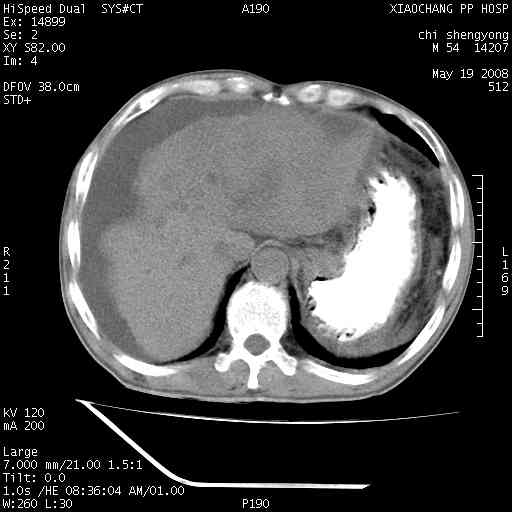

以下是引用zjzjr在2008-5-21 10:52:00的发言:[br]肝左叶巨块型肝癌伴门静脉左支瘤栓形成.肝硬化、腹水,胃底静脉曲张,脾术后改变。

以下是引用随光逐影在2008-5-21 16:20:00的发言:[br]1)肝左叶肝癌伴门静脉左支瘤栓形成,腹膜后淋巴结转移。2)肝硬化、腹水、胃底静脉曲张。3)胆囊炎。4)脾脏缺如,为切除术后所致。